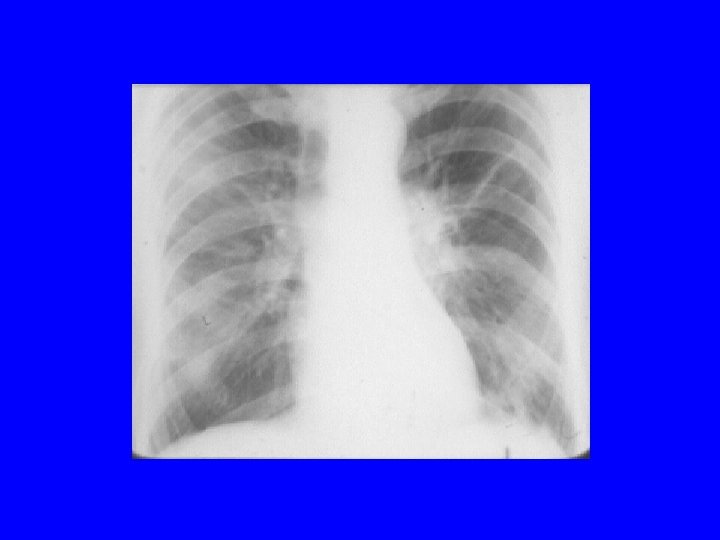

Chlamydia trachomatis xray

C. trachomatis pneumonia • • Neonatal infection presents at 1 -3 months of age Staccato-like cough, rapid respiratory rate NO FEVER Evaluation: minimal chest findings, xray hyperinflation and diffuse infiltrates, peripheral eosinophilia • Associations: atherosclerotic heart disease • Treatment: erythromycin • Prevention: maternal screening